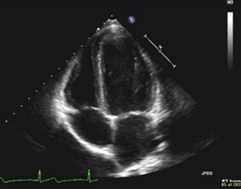

This view is the best to look for pericardial effusions

What is the subxiphoid (subcostal) view?

Left untreated, this finding can progress to this life-threatening clinical diagnosis which presents with hypotension/shock.

(You must name BOTH the current POCUS finding and the diagnosis we worry it might progress into)

What is a pericardial effusion (finding) causing a cardiac tamponade (clinical diagnosis)?